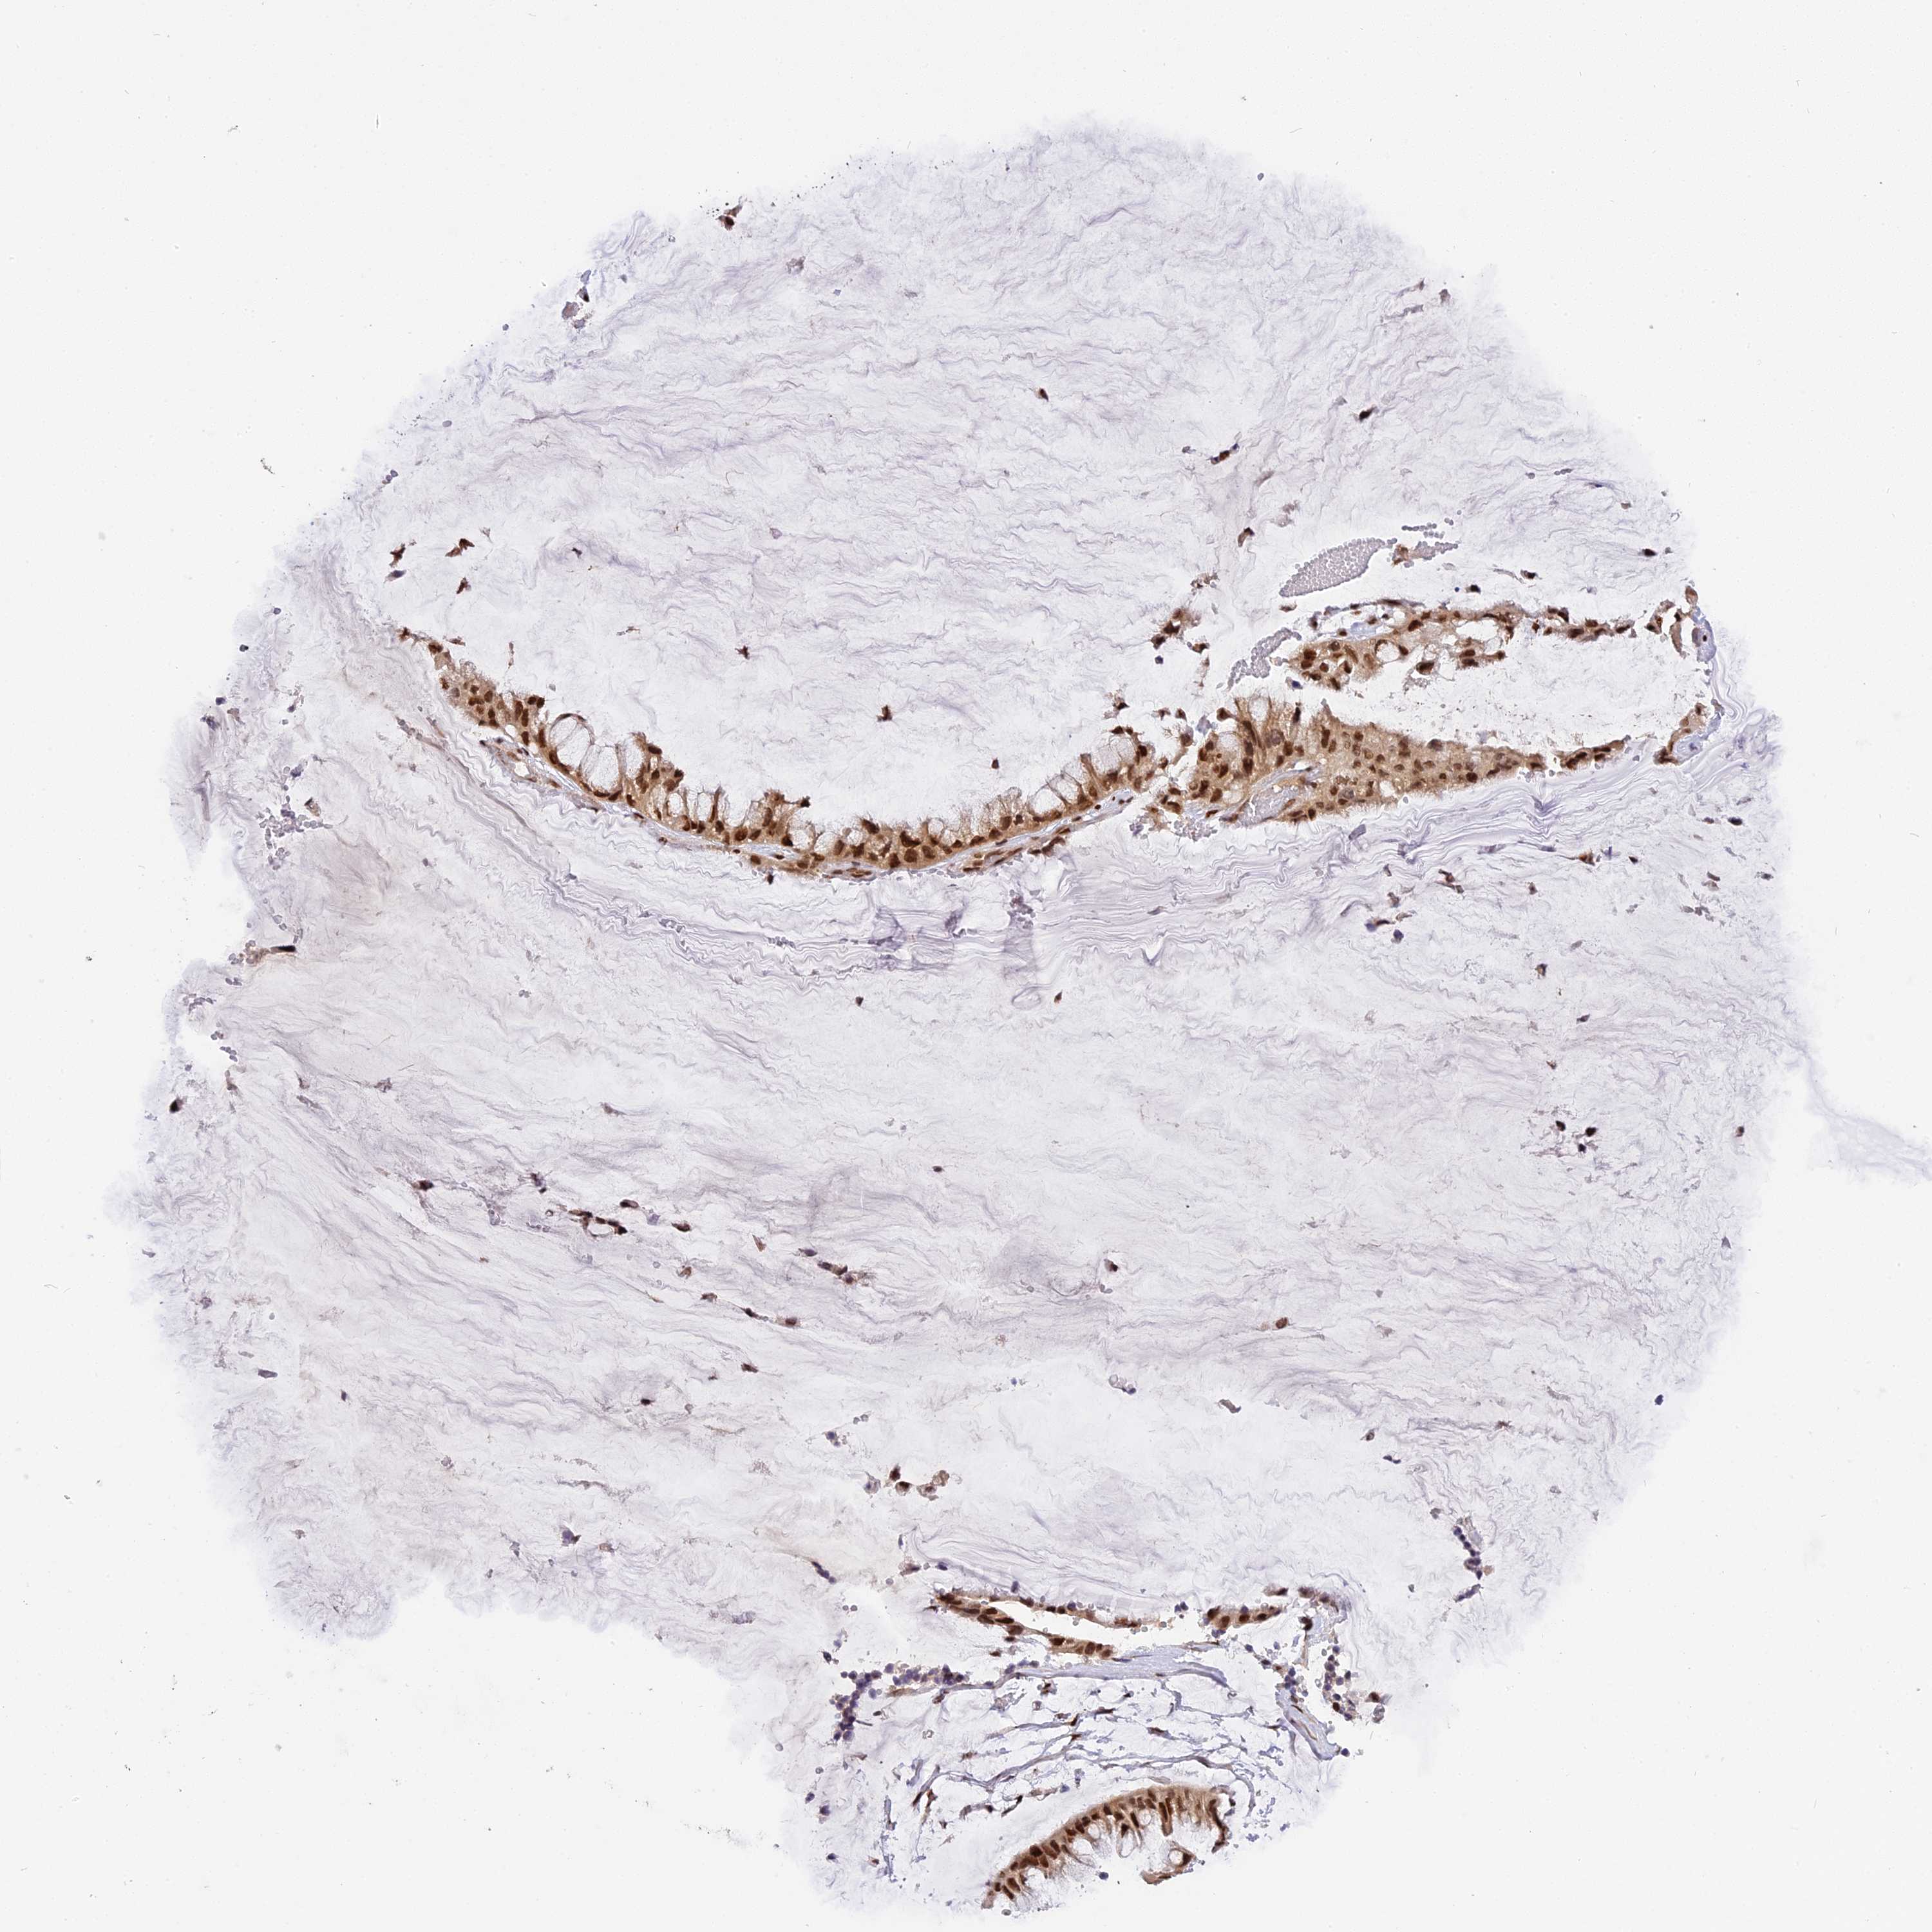

OVARIAN CANCER - Protein expressioni

A mouse-over function shows sample information and annotation data. Click on an image to view it in a full screen mode. Samples can be filtered based on level of antibody staining by selecting one or several of the following categories: high, medium, low and not detected. The assay and annotation is described here.

Note that samples used for immunohistochemistry by the Human Protein Atlas do not correspond to samples in the TCGA dataset.

Antibody stainingi

Antibody staining in the annotated cell types in the current human tissue is reported as not detected, low, medium, or high, based on conventional immunohistochemistry profiling in selected tissues. This score is based on the combination of the staining intensity and fraction of stained cells.

Each image is clickable and will lead to virtual microscopy that enables deeper exploration of all samples and also displays staining intensity scores, fraction scores and subcellular localization as well as patient and tissue information for each sample.

Antibody HPA043488

Staining

High

Medium

Low

Not detected

Intensity

Strong

Moderate

Weak

Negative

Quantity

>75%

75%-25%

<25%

None

Location

Nuclear

Cytoplasmic/membranous

Cytoplasmic/membranous,nuclear

Cystadenocarcinoma, serous, NOS

Carcinoma, endometroid

Cystadenocarcinoma, mucinous, NOS

Carcinoma, NOS